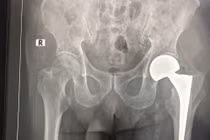

Thay khớp háng cho bệnh nhân 98 tuổi

(khoahocdoisong.vn) - Trước đây, những bệnh nhân trên dưới 100 tuổi nếu không may bị gãy xương ở chân thông thường chịu cảnh tàn phế. Tuy nhiên, từ nhiều năm nay, Khoa Phẫu thuật khớp, Bệnh viện T.Ư Quân đội 108 đã cứu chữa thành công cho nhiều trường hợp bệnh nhân trên dưới 100 tuổi bị gãy xương đùi.